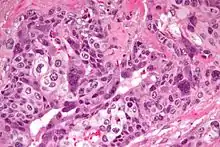

Micrograph of choriocarcinoma showing both of the components necessary for the diagnosis - cytotrophoblasts and syncytiotrophoblasts. The syncytiotrophoblasts are multinucleated and have a dark staining cytoplasm. The cytotrophoblasts are mononuclear and have a pale staining cytoplasm. H&E stain.

Characteristic feature is the identification of intimately related syncytiotrophoblasts and cytotrophoblasts without formation of definite placental type villi. Since choriocarcinomas include syncytiotrophoblasts (beta-HCG producing cells), they cause elevated blood levels of beta-human chorionic gonadotropin.

Syncytiotrophoblasts are large multi-nucleated cells with eosinophilic cytoplasm. They often surround the cytotrophoblasts, reminiscent of their normal anatomical relationship in chorionic villi. Cytotrophoblasts are polyhedral, mononuclear cells with hyperchromatic nuclei and a clear or pale cytoplasm. Extensive hemorrhage is a common finding.